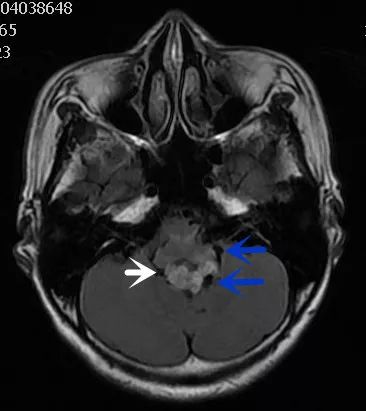

FLAIR图及T1矢状位增强:白色箭头所示小脑延髓池内可见实性占位病变,形态不规则,呈分叶状,病变边界清晰,边缘见血管流空信号影如蓝色箭头所示。

影像描述:小脑延髓池内见不规则异常信号影,呈等及稍长T1长T2信号,内部信号不均,边缘见稍粗大流空信号血管影,FLAIR病灶中心少许片状低信号,增强呈明显强化,DWI不均低信号,ADC不均高信号。小脑半球、延髓、第四脑室受压变形。临近延髓受压变窄,呈长T1长T2信号。

影像诊断:后颅窝实性占位病变,考虑实性血管母细胞瘤。